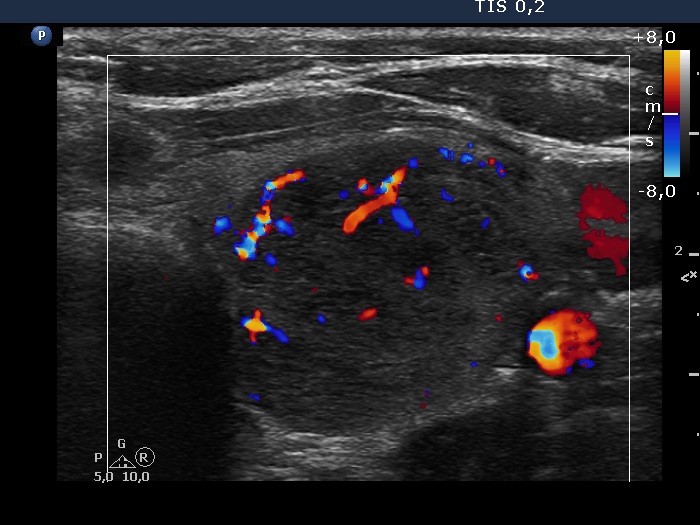

Thyroid cancers - case 649

Follow-up investigation 3 years later (ultrasonographic picture 14)

Middle part of the left lobe, transverse scan, color Doppler mode. The vascularity is increased.